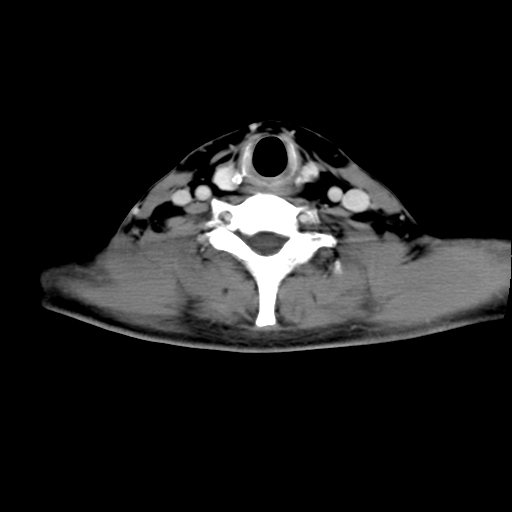

标题: CT24019:男,45岁,发现颈部肿物5个月。 [打印本页]

标题: CT24019:男,45岁,发现颈部肿物5个月。

男,45岁,发现颈部肿物5个月,彩超示:双侧颈部及下颌部软组织增厚。

考虑双侧颈项部良性对称性脂肪增多症。